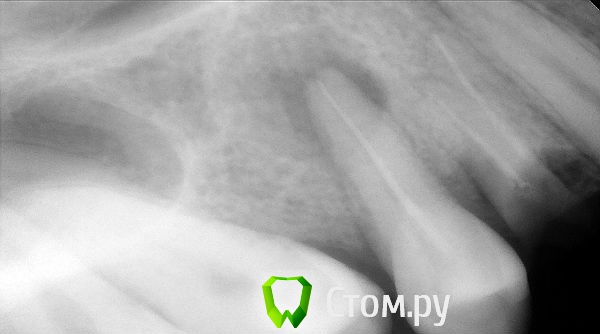

Romanson Опубликовано 28 августа, 2014 Автор Поделиться Опубликовано 28 августа, 2014 (изменено) Добрый день. Выложите снимок и фото. в переднем отдетеле желательно удалить и одномоментную имплантацию провести для предсказуемого результата, после имплантации можно сделать временную коронку.Ни снимка ни фото конкретно по этой ситуации нет.Но вот, примерно похожая ситуация. Пациентку смущает отсутствие коронковой части зуба 1.4План был такой - заняться перелечиванием зуба 1.5, параллельно удалить 1.4, дождавшись образования первичной кости 1.4 и заживления периапикальных тканей 1.5 поставить имплант. Чтобы пациентка улыбалась, хотелось придумать какую-то временную конструкцию. Вот по этой части вопрос в первом сообщении.Вопрос не по текущей теме: если ситуация как на приложенном снимке, то имплантация 1.4 противопоказана же, т.к. рядом есть очаг инфекции 1.5? Изменено 28 августа, 2014 пользователем Romanson Ссылка на комментарий

togrul Опубликовано 28 августа, 2014 Поделиться Опубликовано 28 августа, 2014 Ни снимка ни фото конкретно по этой ситуации нет.Но вот, примерно похожая ситуация. Пациентку смущает отсутствие коронковой части зуба 1.4План был такой - заняться перелечиванием зуба 1.5, параллельно удалить 1.4, дождавшись образования первичной кости 1.4 и заживления периапикальных тканей 1.5 поставить имплант. Чтобы пациентка улыбалась, хотелось придумать какую-то временную конструкцию. Вот по этой части вопрос в первом сообщении.Вопрос не по текущей теме: если ситуация как на приложенном снимке, то имплантация 1.4 противопоказана же, т.к. рядом есть очаг инфекции 1.5?да все правильно. Ссылка на комментарий